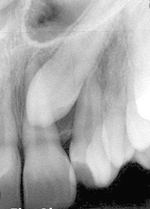

Caninii sau molarii de minte apar pe radiografia panoramică, deși nu sunt observabili în cavitatea bucală. Aceștia sunt complet sau parțial sub os și, de cele mai multe ori, sunt înclinați puternic față de ceilalți dinți.